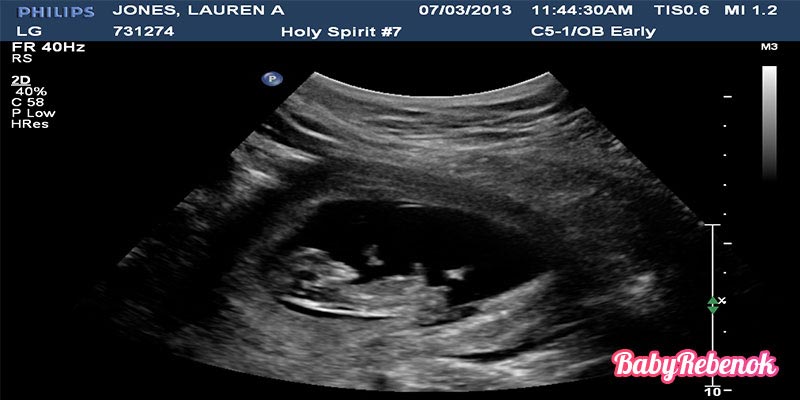

16 неделя беременности УЗИ и анализы

На 16 неделе беременности уже отлично видны шевеления и движения крохи во время ультразвукового обследования. Также видна мимика малыша и на этом сроке можно определить пол ребенка.

16 неделя беременности: фото плода, УЗИ

Как часто нужно делать УЗИ на 16 неделе беременности?

На 16 неделе беременности рекомендуется провести второе плановое УЗИ. Оно позволяет оценить развитие плода, проверить его органы и системы, а также выявить возможные патологии.

В 16 неделю беременности многие женщины делают УЗИ, чтобы увидеть своего малыша и узнать о его развитии. Рекомендуется записать на видео или сделать фотографии во время УЗИ. Это позволит вам сохранить воспоминания о первых моментах видения своего ребенка и поделиться этими эмоциями с близкими.